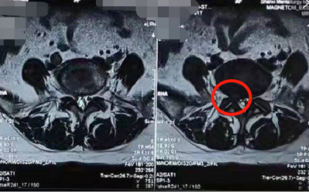

术前影像学资料

当时由熊东主任接诊后,发现他腰5骶1椎间盘突出,并且已经严重压迫神经根,这种情况建议尽快进行手术解压,于是就尽快为他做了非常微创的椎间孔镜手术。手术效果非常好,这次来复查时健步如飞,走路和正常人完全一样,腿部疼痛已经消失。